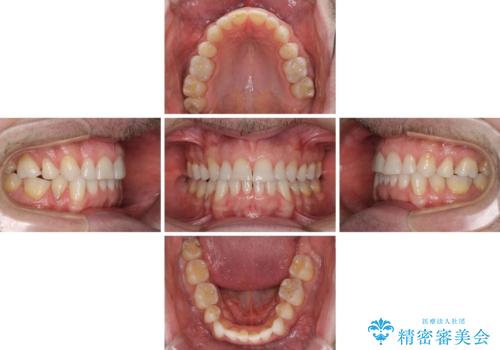

- 上下前歯の叢生を気にして来院された患者様です。

抜歯矯正をした後戻りということで、歯列不正はそれほど大きくなかったため、インビザライン・ライトを用いて矯正治療を行うこととしました。

前歯のデコボコが残っており、シミュレーション通りに動いていない部分がありましたが、再矯正であることやご本人の満足いくところまでデコボコが改善されたとのことで、治療を終了することとしました。